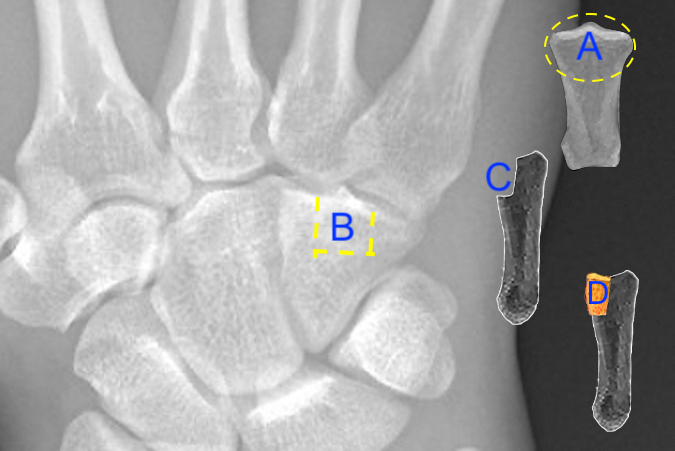

Related Anatomy

- The middle phalanx consists of a distal phalangeal head that articulates at the distal interphalangeal (DIP) joint with the distal phalanx, a narrow diaphyseal shaft, a proximal metaphysis, and a base that articulates at the PIP joint with the proximal phalanx. The base of the middle phalanx has a dorsal and volar lip.

- The ligaments associated with the middle phalanx at the DIP and PIP joints are the dorsal capsule, the collateral ligaments (proper and accessory collaterals), and the volar plates. The retinacular ligament that runs obliquely along the middle phalanx is the final ligament associated with the middle phalanx.

- Tendon attachments include the flexor digitorum superficialis tendon, which is inserted by two slips on either side of the base of the middle phalanx and the extensor tendons. The central slip inserts into the dorsal lip of the base of the middle phalanx, and the terminal extensor tendon traverses the middle phalanx and then inserts into the distal phalanx. The median band of the extensor digitorum tendon passes to the base of the middle phalanx.

- There is a basic anatomical difference between the proximal and middle phalanges: the proximal phalanges have a longer, wider intramedullary canal with more cancellous bone, whereas the middle phalanges have a shorter, narrower intramedullary canal with more cortical bone.16 In general, fractures through cortical bone heal slower than fractures in cancellous bone.